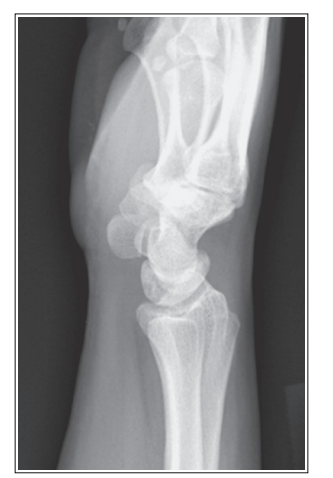

the distal capitulum surface is demonstrated too far distal to the distal surface of the medial trochlea and the radial head is placed too far posteriorly to the coronoid process

Proximal humerus is elevated

Distal capitulum is too far proximal to the distal medial trochlear surface of the radial head is too far anterior to the coronoid process

Distal forearm is depressed